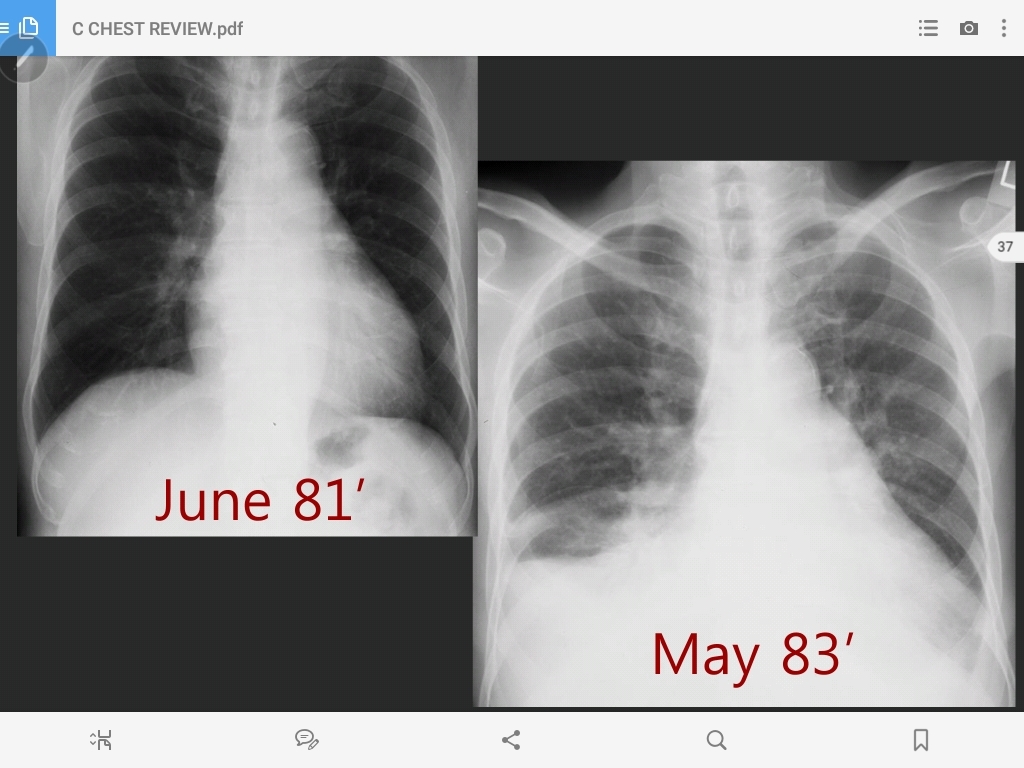

histoplasmosis

hilar lymph node enlargement and a peripheral granuloma (Ranke complex)